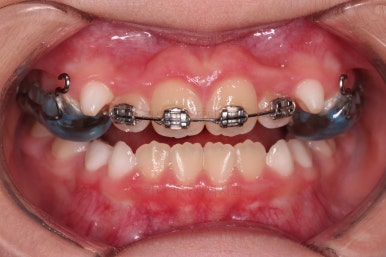

위턱뼈가 가로로 넓어지니 앞니 사이에도 공간이 많이 생겼네요.

부분적으로 교정장치를 부착해서 당사자가 제일 고치고 싶어햇던 앞니 부분을 가지런하게 하기 시작했어요.

위턱뼈가 앞으로도 점점 나와서 처음 보다는 반대교합 경향이 개선되고 있는게 보이네요.

앞니도 굉장히 가지런해졌고요.

반대교합 경항도 거의 없어졌어요.